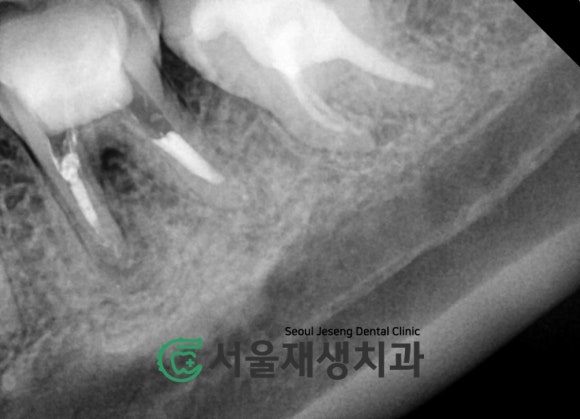

주기적인 뿌리 청소와 소독으로

치근단염증이 줄어드는 중입니다.

=뼈가 재생되는 중입니다!

![[재신경치료] 예전에 신경치료 받은 치아....치근단 절제술이나 발치를 해야 한다는데요?! (신촌 서울재생치과) 관련 이미지 9](https://pub-9f2bb3498faf4d1d8714b41df24753e3.r2.dev/content/clinics/archive/nqmm0udu86/naver_blog/honeybeevuvu/assets/by_hash/57802acd489d8607a469b39349d9893d3bec375313d9e03f0d2653e996fb86cf.jpg)

시간이 지날수록

뿌리 끝에 달려있던

까만 주머니의 크기가

감소합니다!

염증 주머니가 작아지는 것은

골조직의 재생을 의미합니다^^